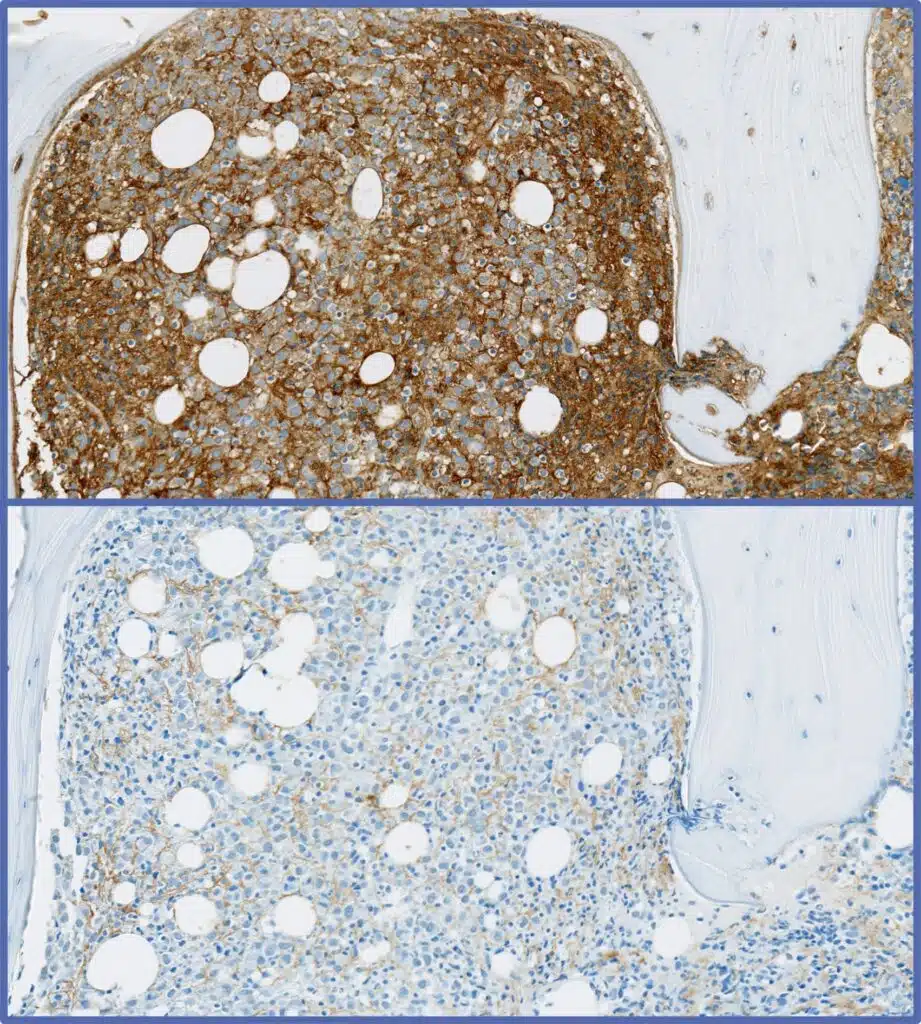

Histopathology analysis with markers such as CD138, kappa, lambda run in CLIA accredited laboratories

Multiplex / simplex IHC

250+ biomarkers / protocols

Strong immuno-oncology simplex & multiplex panels